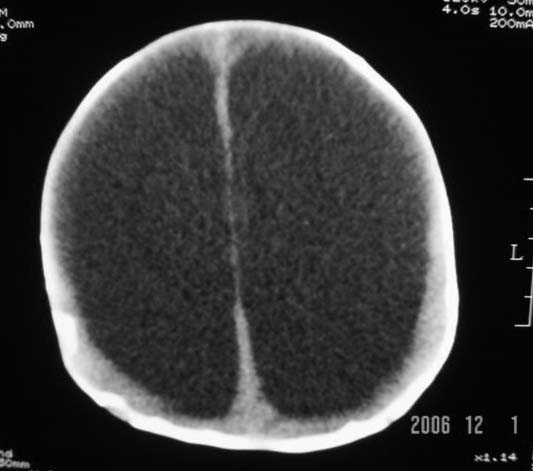

3m,出生时有新生儿吸入性肺炎、hie、化脓性脑膜炎,近一个月发现头围增大(51cm),无恶心呕吐。

3m,出生时有新生儿吸入性肺炎、hie、化脓性脑膜炎,近一个月发现头围增大(51cm),无恶心呕吐,脑室系统全程扩张,脑皮质变薄,结合病史考虑交通性脑积水

3m,出生时有新生儿吸入性肺炎、hie、化脓性脑膜炎,近一个月发现头围增大(51cm),无恶心呕吐,脑室系统全程扩张,脑皮质变薄,结合病史考虑重度交通性脑积水。